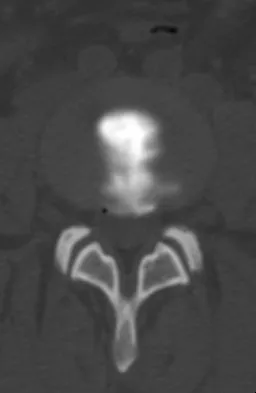

Figures 5a and 5b show the radiograph and MRI scan of a patient who has severe mechanical neck pain but no neurologic problems. Biopsy and work-up show the lesion to be a solitary plasmacytoma. Treatment should consist of

Plasmacytoma is very sensitive to radiation therapy and given the complexity of the resection and complications of surgery in the given location, radiation therapy is preferred. However, the patient has clear loss of bony structural integrity, and resultant instability would persist even with tumor irradiation; therefore, posterior stabilization is warranted. Chemotherapy and bone marrow transplant are reserved for systemic disease with multiple myeloma. Corwin J, Lindberg RD: Solitary plasmacytoma of bone vs. extramedullary plasmacytoma and their relationship to multiple myeloma. Cancer 1979;43:1007-1013.